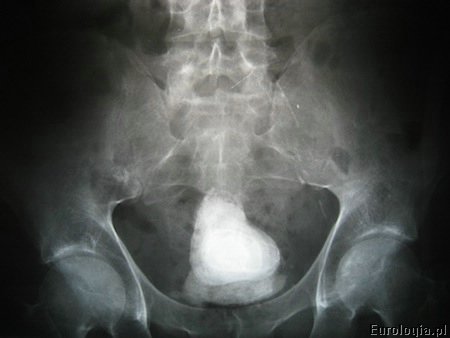

Fot. Zdjęcie RTG z widocznym złogiem w pęcherzu moczowym